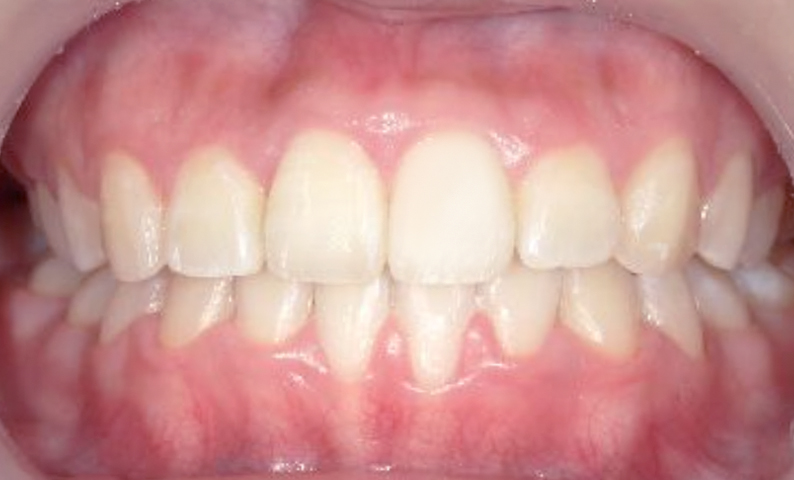

症例_004 上顎だけの部分矯正

治療期間:6ヶ月金額:27万円+税男性出っ歯上の前歯だけ

| Before | After |